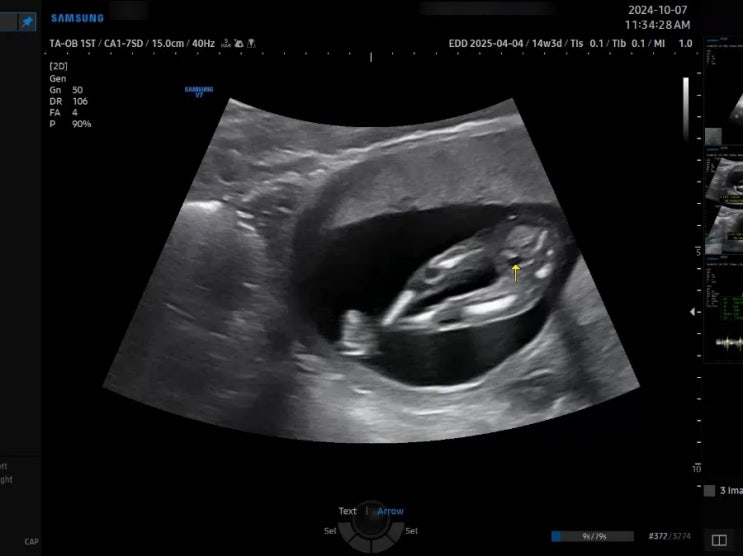

임신 16주 차 성별 확인, 자궁경부 길이 짧음, 다리 저림 / 큐트루

안녕하세요 큐트루예요. 임신 16주 차 2차 기형아 검사와 성별 확인, 자궁경부 길이 짧음, 다리 저림 포스...